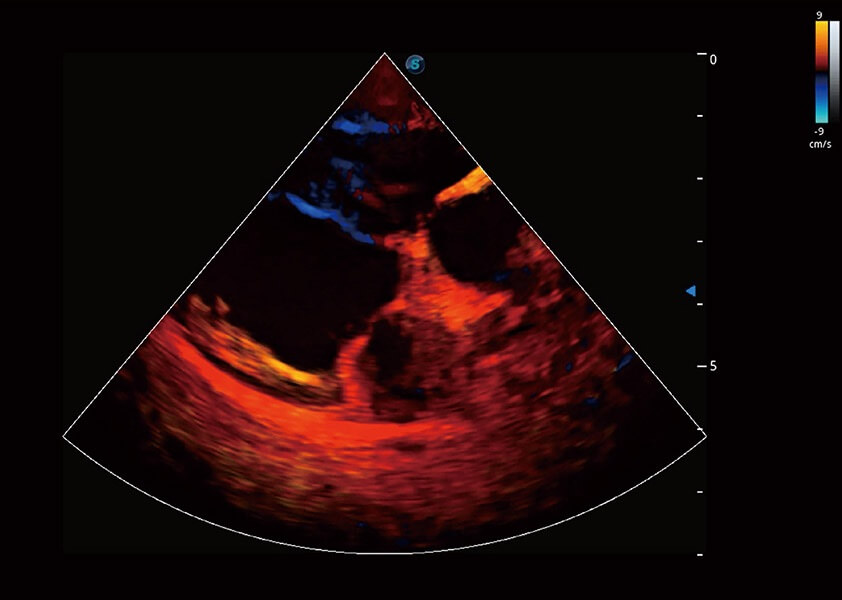

ProPet 60 作为一款高端台式动物超声设备,为动物医生的日常诊断提供了一系列贴合动物临床需求、解决临床实际问题的高级成像功能。凭借全系列高清探头,满足医生对腹部、心脏、生殖、浅表、肌骨等成像的所有需求,切实帮助您提升检查效率,提高诊断信心。

动物是人类最亲密的朋友和最值得信赖的伙伴。乐玩lewin国际也一直致力于探索动物专用的超声影像解决方案。 全新推出的ProPet系列,是乐玩lewin国际在动物超声影像智能化、专业化、精准化的一次跨越式革新。动物不能用言语来表述自己的不适,通过超声影像,ProPet系列搭建了动物医生与不同物种沟通的“桥梁”,为动物医生注入了“治愈之力”。